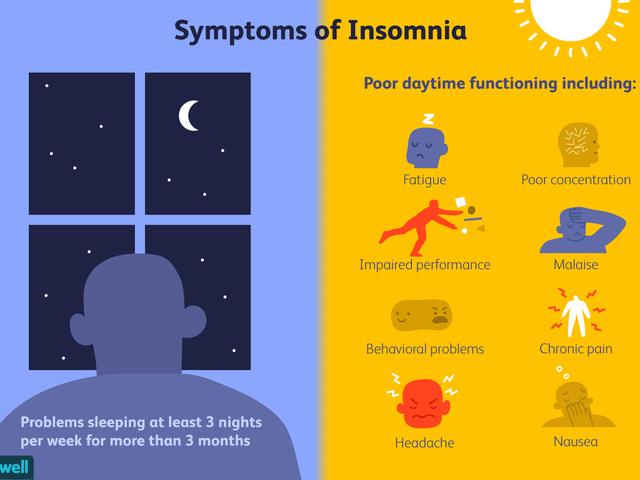

まず、睡眠不足とは何か、どのように現れるのかを知ること。

要するに、睡眠不足が続くか、睡眠の質が低下することによって引き起こされるのが睡眠不足であり、成人の通常の睡眠スケジュールは一晩あたり7~9時間と推奨されている。定期的に7時間未満の睡眠しかとれないと、やがて健康が損なわれ、全身に影響を及ぼします。睡眠不足は、夜更かしや不眠症、根本的な睡眠障害によって引き起こされることがある。

睡眠不足の明らかな症状には次のようなものがある:

過度の眠気

頻繁にあくびをする

イライラ

:: 日中の疲労

めまいと頭痛、耳鳴り

若者はコーヒーを好んで飲む。コーヒーに含まれるカフェインが脳を興奮させ、気分を高揚させる。日中起きると元気がなく、睡眠不足による疲労と闘うためにまたコーヒーを飲む。このような慢性的な睡眠不足の悪循環は、体の内部システムに支障をきたし、上記のような初期症状や徴候以上のものを引き起こす。